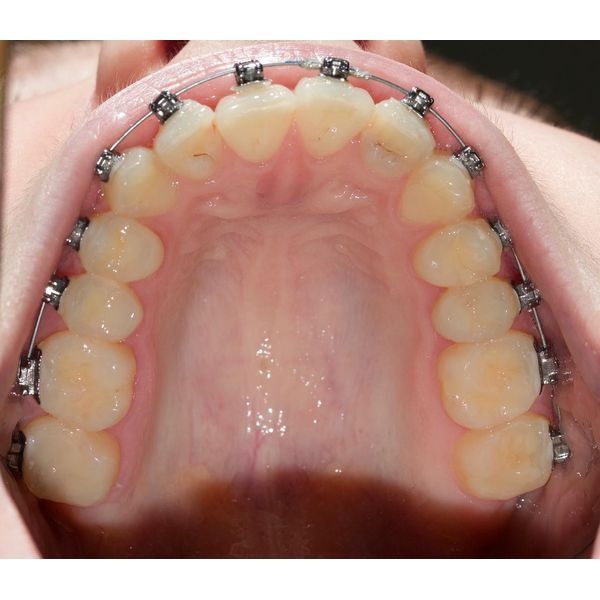

После обезболивания и изоляции зубов их отполировали, удалили пломбы и кариес. После дезинфекции и высушивания поставили пломбы и послойно отреставрировали зубы. Каждый слой засветили со всех сторон по 20 секунд. В конце пломбы отшлифовали и отполировали, после чего покрыли фторлаком, защищающим эмаль. На каждый зуб (их было два) ушло по 2 часа. Лечение проходило в течение месяца.

Уже после первого этапа лечения появились улучшения:

- боль уменьшилась;

- интенсивность реагирования на раздражители понизилась;

- пища стала реже застревать.

Через месяц после завершения лечения пациентка отметила, что чувствует себя хорошо и приём пищи больше не вызывает неприятных ощущений. Ей назначили контрольный осмотр через полгода с учётом годовой гарантии. Со временем провели имплантацию, протезирование и выровняли прикус.